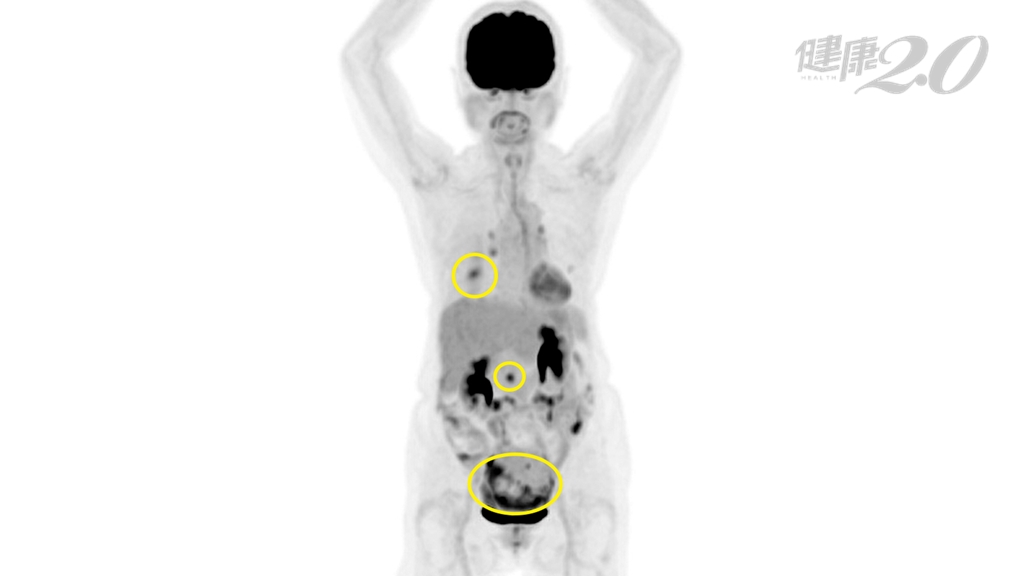

楊朝瑋表示,該患者經正子電腦斷層造影檢查,「擒敵先擒王」,結果發現其骨盆腔有團惡性腫瘤範圍約10公分,腹腔淋巴也有小於1公分的淋巴結,轉介至婦科做超音波檢查,卻看不到卵巢和輸卵管有異常;經跨科會議後,決定進行開刀,果然是卵巢和輸卵管長了腫瘤。

▲正子電腦斷層造影檢查找到癌細胞源頭。